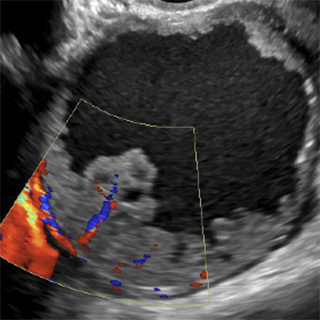

- Ultrasound (US) - the primary imaging modality, which is optimized for high sensitivity

Both O-RADS US and O-RADS MRI employ lexicon terminology for describing the imaging characteristics of ovarian/adnexal lesions and data-based risk assessment categories to assign a risk of malignancy. The goal of the O-RADS system is to optimize ovarian cancer outcomes while minimizing unnecessary surgery in patients with adnexal lesions.